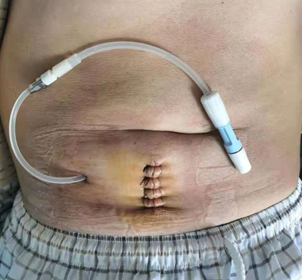

既往腹部手术切口,多采用普通丝线进行间断缝合。术后2周左右需二次拆线,长期会留有明显的瘢痕,见图 1。

图 1 传统腹透置管后的切口和简单缝合方法,图片来自于网络。

手术当晚或次日早期下床康复,切口美观,无需拆线,如图3。细节决定成败。

图 3 采用倒刺线进行美容缝合后的手术切口,术后逐步愈合遗留很淡瘢痕。